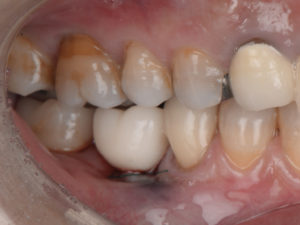

【インプラントのトラブルを解決した症例】

過去に他院でインプラント治療を受けられましたが、「インプラントが外れる」「インプラントが割れる」などのインプラントトラブルでお困りになり、当院に来院されました。 すでに、右上のインプラントのセラミック…